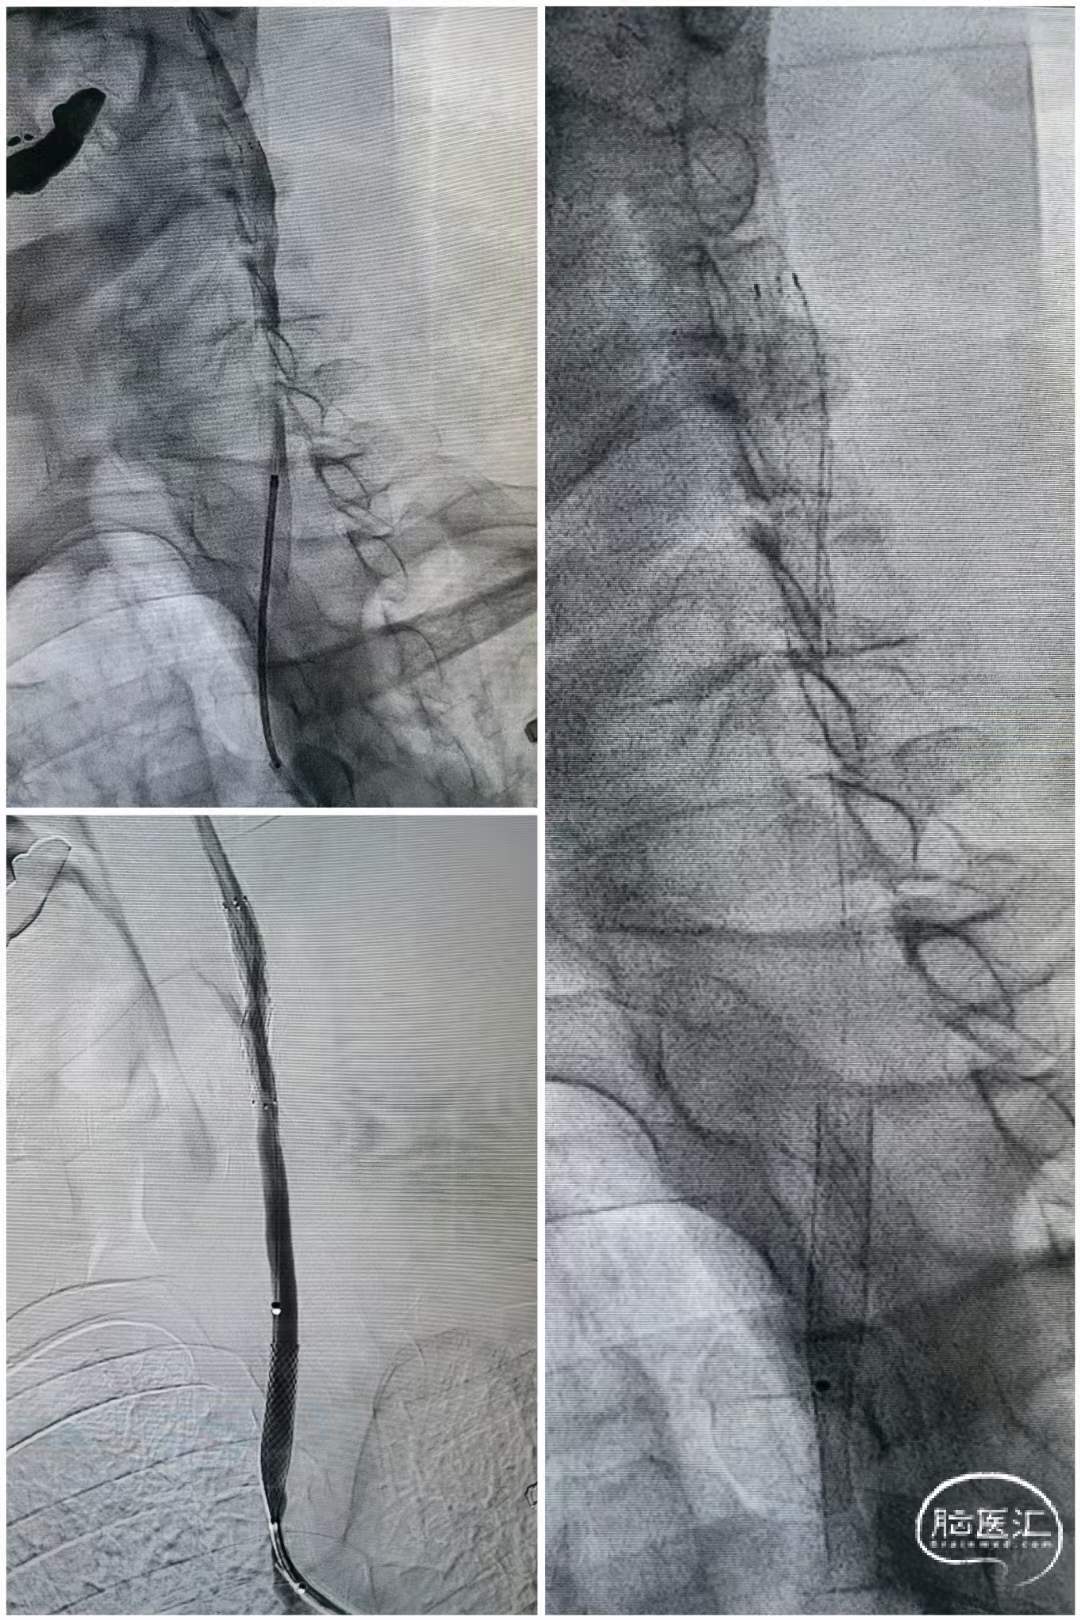

术中操作

右侧慢性闭塞处理

跨越狭窄段释放支架,造影可见右侧闭塞再通。